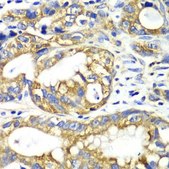

Application:

immunohistochemistry: 1:50-1:200, western blot: 1:500-1:2000